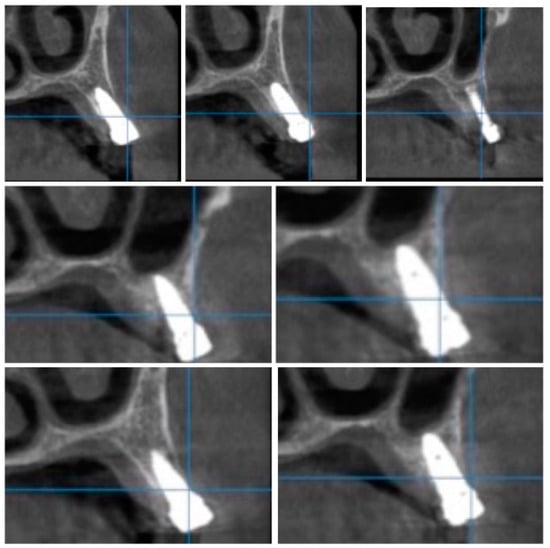

After 60 days of healing process, new CBCT images were recorded in order to assess bone density changes that might have occurred near the implant sites (Figure 9, Figure 10 and Figure 11).

Figure 10.

Random CBCT sections with pulse electromagnetic healing caps in position.

Figure 11.

Random CBCT images with pulse electromagnetic healing caps in position.

In the next phase of the study, after a healing period of 60 days, new measurements regarding bone density were recorded (Figure 12 and Figure 13). To avoid the metal artifact/beam hardening effect created by implants, new measurements were recorded at a 2 m distance from the implant site.

Figure 12.

Bone density around dental implants at 60 days following surgery with conventional healing caps.

Figure 13.

Bone density around dental implants at 60 following surgery with MED™ electromagnetic healing caps.